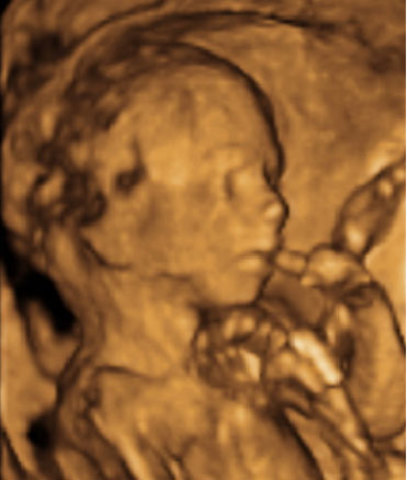

Los ojos del bebé se comienzan a abrir y cerrar regularmente pero aun cuando el color ya está genéticamente determinado este solo se podrá conocer después de los 6-8 meses de nacido. Su bebé alterna ciclos de sueño/vigilia cada 20 a 30 minutos. Los movimientos fetales se hacen muy obvios cuando usted se relaja, sentada o acostada, especialmente durante la noche. Los rasgos faciales son muy claros

• Semana 29

Semana 29